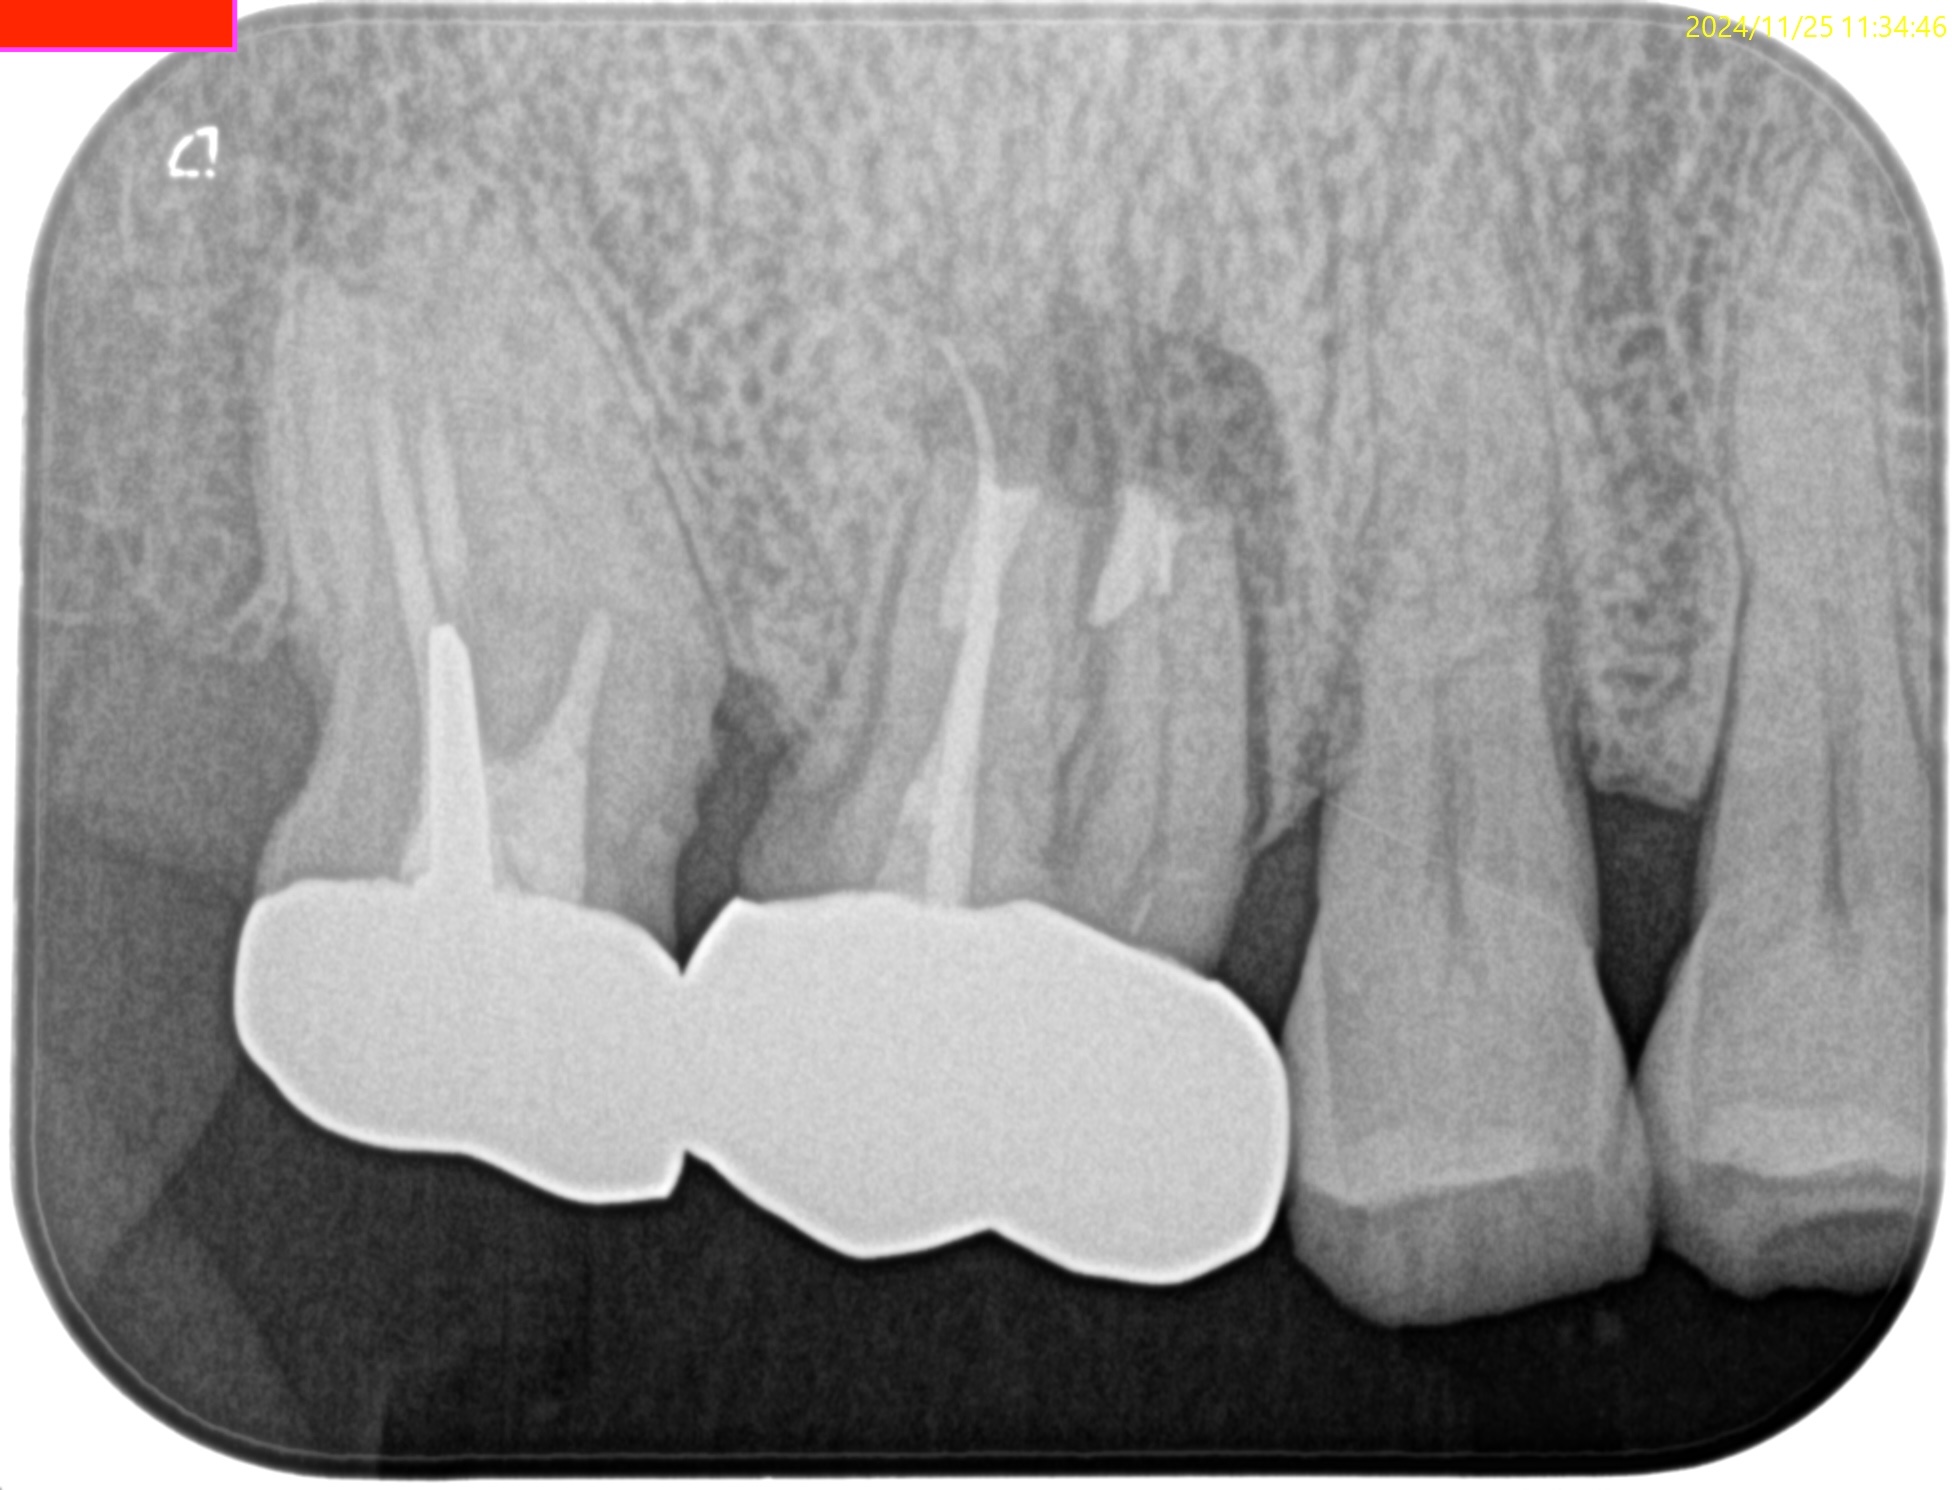

Pre-op PA(2024.11.25)

MBは形成されていない。

ということは通常は根管治療だがSinus tractの存在が治療をApicoectomyへ流れさせている。